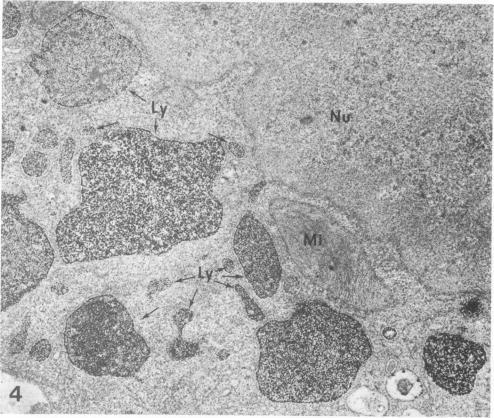

Previous electron-microscopic studies on the liver have shown that following excessive administration of iron to experimental animals, small particles believed to represent ferritin and/or hemosiderin (electron-dense iron-containing particles [IPs]) accumulate in membrane-bound bodies--many with a lysosome-like structure--in liver parenchymal and Kupffer cells. Further identification of the IP-containing bodies has been facilitated by the application of histochemical techniques for the demonstration of acid phosphatase. The results have shown that reaction product was deposited over organelles similar in appearance to the IP-containing ones, indicating that they were lysosomes. However, the granular nature of the reaction product makes it difficult or impossible to decide whether IPs are present simultaneously with reaction product in the organelle. In order to clarify this qualitative aspect, x-ray microanalysis has been utilized to identify iron and lead (reaction product) in the various structures thought to represent lysosomes. The results indicate that all IP-containing bodies also show the presence of reaction product, and thus can be regarded as lysosomes. However, in the parenchymal cells there may exist a small population of iron-deficient lysosomes (only lead could be shown). The latter may correspond to "primary lysosomes."

Am J Pathol. 1979 Aug;96(2):625-40.

PMID:474712

原文链接:https://pmc.ncbi.nlm.nih.gov/articles/PMC2042434/